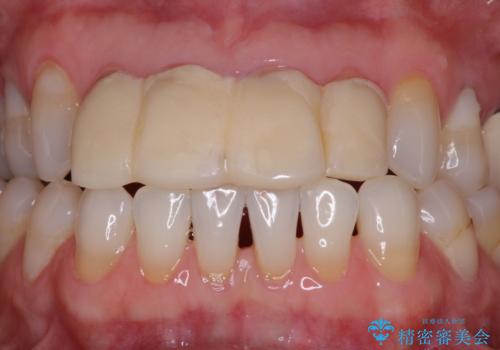

- 自宅近くの歯科医院にて前歯の詰め物が外れたことを機会に、オールセラミッククラウンへの変更を決断して4歯を仮歯に替えたものの、あまりに汚くて恥ずかしいとのことで来院された患者様です。

歯の形成量は不十分で形態は不自然、境目は不適で歯肉が腫れていたため、新しい仮歯に替えた後に歯肉の腫れが引くのを待ち、オールセラミッククラウンにて補綴することとしました。

前医で仮歯を装着する前の口元の写真をいただき、咬み合わせや形態を参考にしながら仮歯で仕上がりをイメージし、最終的に満足のいくオールセラミッククラウンを装着することができました。